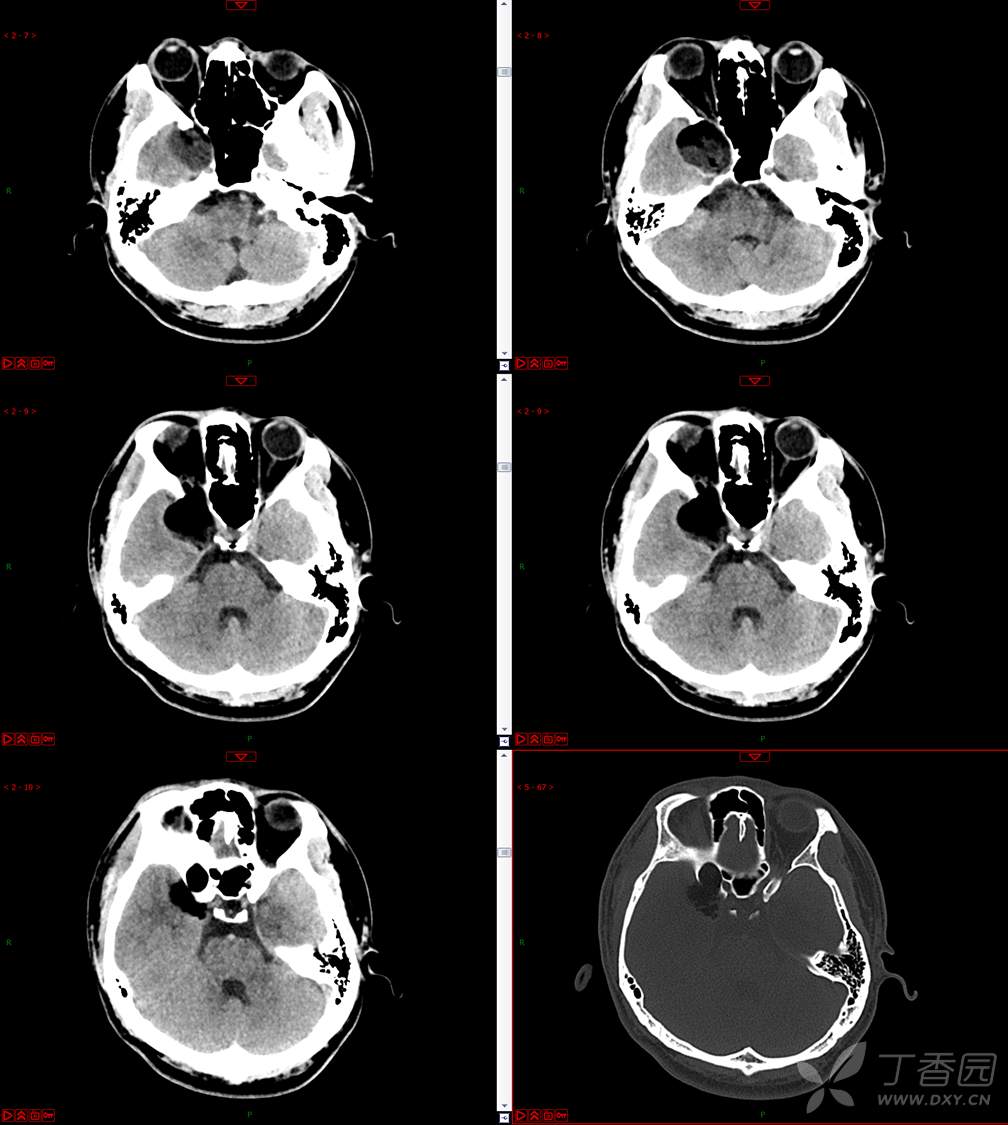

【影诊笔记534】青年男性,视物模糊就诊,CT、MRI、MRS齐全,请分析~~~

主 诉:视物重影5天。

现病史:患者5天前无明显诱因出现视物重影,表现为右视时视物成双,无头痛、头晕,无恶心、呕吐,无面部麻木、饮水呛咳等,于当地医院就诊,行颅脑MR示“颅内占位性病变”,现为求进一步治疗来诊。患者病来精神可,饮食、睡眠正常,体重无明显变化。